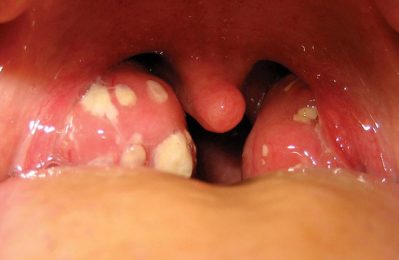

Viêm amidan mãn tính có nguy hiểm không? Tuấn tôi thường nhận được câu hỏi này từ bà con, và thực tế là bệnh không...

Viêm amidan mãn tính có thể gây khó khăn trong việc sinh hoạt hàng ngày. Tuấn tôi hiểu rằng nhiều bà con đang thắc mắc...